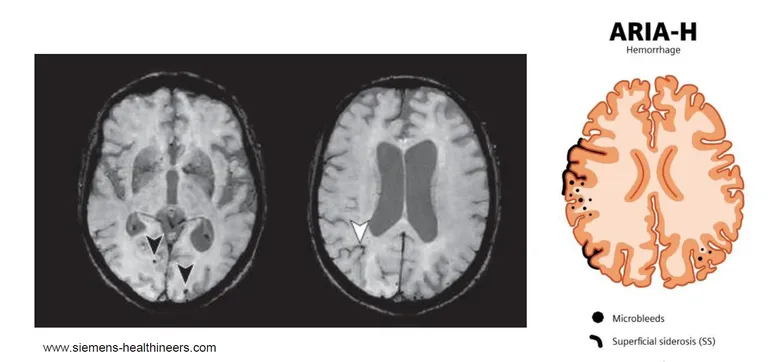

In parallel, compromised vessel integrity can allow small amounts of blood to escape into surrounding tissue. Iron-sensitive MRI sequences, such as T2* or susceptibility-weighted imaging (SWI), reveal microhemorrhages and linear superficial siderosis, collectively classified as ARIA-H (hemorrhage).

The ARIA-E severity grading system—mild, moderate, or severe based on lesion size—was established during early trials and remains valid today. ARIA-E and ARIA-H can occur simultaneously. While ARIA-E typically has a transient course and resolves on follow-up imaging, ARIA-H findings (microbleeds and superficial siderosis) may persist on MRI for prolonged periods.